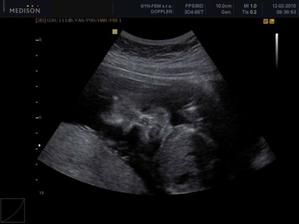

30.12. Jsem se byla zaregistrovat k porodu u Apolináře. ROK 2010 🙂 TO SE BUDOU DÍT VĚCI. 12.1. interní vyšetření + EKG a odběr - všechno OK, 14.1. UTZ žil kvůli natékání nohou (už ráno mám kotníky jako bambule). Výsledek: tromboza nehrozí UF!, nedomýkavost chlopní tepen, pže tělo je víc zatíženo. Doporučeno: nosit těhu punčochy, hodně pít, víc chodit, málo sedět a stát. Pak jsem utíkala na gyn na triplle testy a sestra mě objednala i na velký UTZ kam půjde i manža a budeme mimíska mít na DVD. Jsme oba natěšený! 20.1. UTZ ledvin - vše v pořádku. Tak velký UTZ proběhl OK. Nechceme vědět co to bude tak to stále nevíme 🙂)) . Triplletesty jsou taky v pořádku. 18.2. poradna - tak jsem měla nízký tlak 🙂)) jindy ho mám vysoký tak jsou trošku zmatený. Říkám, že mají blbý tlakoměr. Gynekologicky a miminkovsky všechno dobrý. 21.2. domluveno jméno pro klučíka - TOMÁŠEK .... ještě tu holčičku 😉)).